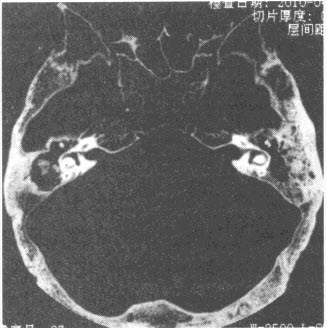

- 单项选择题患者,男,63岁,进行性听力下降1年,右耳流脓10年。CT检查如图,诊断为()

- C

- CT见中耳腔内不规则软组织肿块影,周边骨